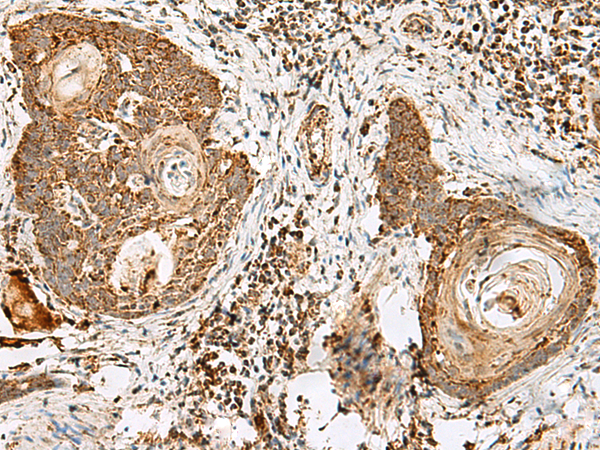

IHC positive control: |

Human esophagus cancer |